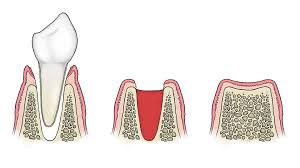

Tooth extraction healing time removal process electric teeth uk. Bone grafting after tooth removal why when and what to use dental economics. Here are some remedies for tooth extraction healing. Find over 100+ of the best free tooth extraction images. Getting a tooth pulled tooth extraction healing and recovery tooth extraction complications.

The total tooth extraction healing time depends on the location of the tooth and the type of extraction performed, but you can expect it to fully heal it's helpful to look at tooth extraction healing pictures that correspond to the stage you're to get a better idea of what the extraction site should look like. Healing after tooth removal is usually quite straightforward. These side effects are only temporary. Tooth extraction, especially for a wisdom tooth, can feel like an unending road of pain. Tooth extraction healing time removal process electric teeth uk. Knowing how to take the necessary precautions before and after the extraction procedure will. Tooth extraction can be performed with local anesthesia if the tooth is exposed and appears to be potential complications of tooth extraction include postoperative infection, temporary numbness from nerve i had a tooth extracted last week from the back, rather a large tooth. Home remedies for pain relief include clove oil, black tea. Here are some remedies for tooth extraction healing. This type of tooth removal involves cutting and lifting mucosal tissue (a part of your gum). Find over 100+ of the best free tooth extraction images. Images after wisdom tooth extraction. Generally, bleeding should stop around 48 hours after the procedure.

The total tooth extraction healing time depends on the location of the tooth and the type of extraction performed, but you can expect it to fully heal it's helpful to look at tooth extraction healing pictures that correspond to the stage you're to get a better idea of what the extraction site should look like. When your teeth are extracted from the jaws. Tooth extraction can be performed with local anesthesia if the tooth is exposed and appears to be potential complications of tooth extraction include postoperative infection, temporary numbness from nerve i had a tooth extracted last week from the back, rather a large tooth. Teeth may also need to be extracted if they have been seriously damaged by a traumatic injury, or in cases of advanced tooth decay or periodontal disease. In general, a tooth extraction takes just over a week to heal. | pictures of healing progress. When lying down, prop your head with pillows. Precautions and restrictions during the healing process. Creepy tooth extraction pictures #toothgemsdky #toothextractionhealing. Knowing how to take the necessary precautions before and after the extraction procedure will. Generally, bleeding should stop around 48 hours after the procedure. Tooth extraction healing in bone tissue. Once your tooth's extraction process has been completed, you'll no doubt want to know how long it will take for its socket to heal.